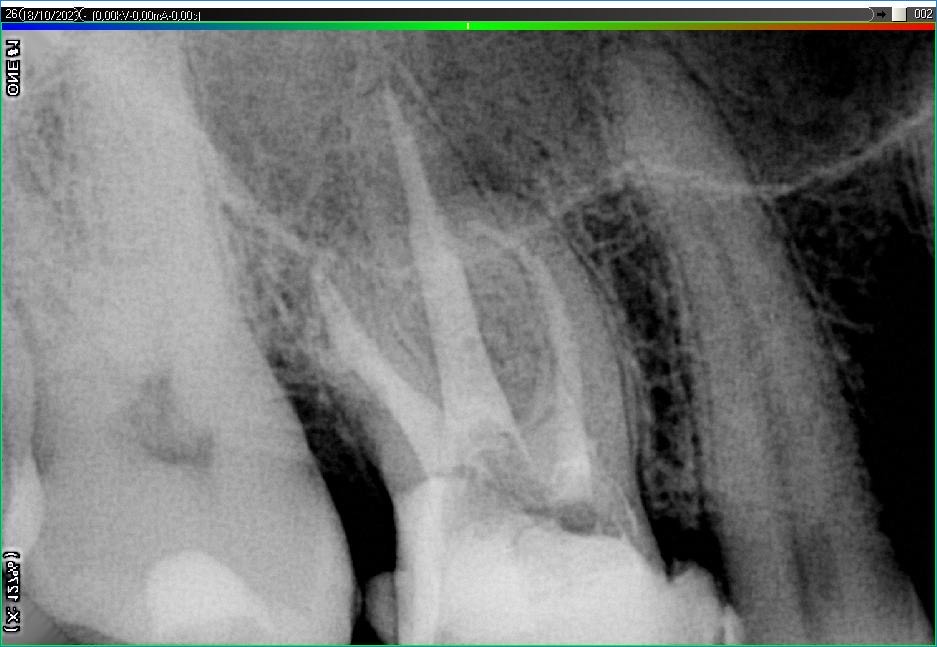

Вилучення інструменту з каналів зуба